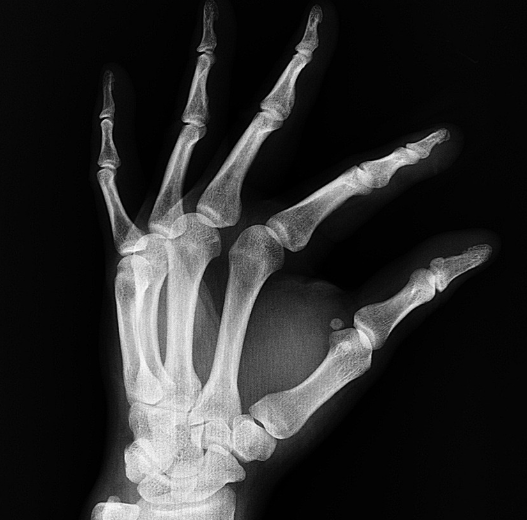

- 척추뼈, 손목, 고관절 골절 위험 증가